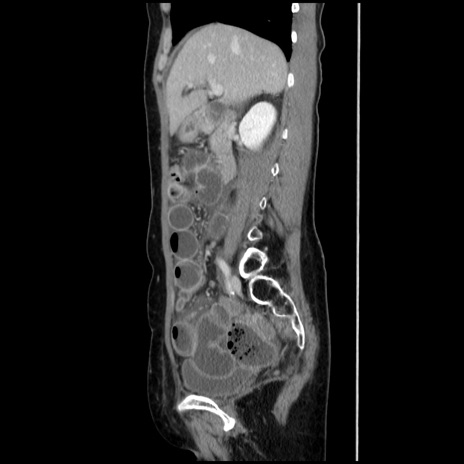

症例32(矢状断像)

【症例】40歳代 女性

【主訴】上腹部痛、嘔気・嘔吐

【現病歴】約9時間前頃から急に上腹部痛、嘔気、嘔吐が出現。改善しないため救急要請。

【既往歴】子宮頚癌(広汎子宮全摘術、放射線療法)、腸閉塞

【身体所見】腹部:平坦、軟、腸雑音亢進、上腹部を中心に腹部全体に圧痛あり。

【データ】WBC 8400、CRP 0.03

冠状断像